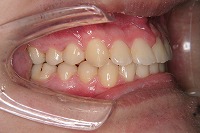

左

反対咬合と下顎が出ている事を主訴に来院された、初診時18歳1か月の男性です。診断「上顎骨の後方位による骨格性反対咬合」非抜歯での矯正治療と、下顎を後退させる外科手術を併用して治療を行いました。